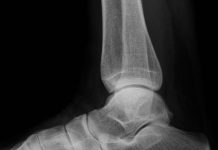

Gezocht: mensen met hielspoorklachten

De afdeling Orthopedie van de Sint Maartenskliniek is bezig met de evaluatie van de behandeling bij mensen met chronische hielspoorklachten, ook wel fascïitis plantaris...